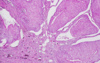

Wilms tumor Microscopic features (3)

- Triphasic pattern*

- Primitive blastema (small/dark undifferentiated cells)

- Epithelial component (abortive tubules/glomeruli)

- Stroma (Fibrous or myxoid patterns; may contain mesenchymal elements (cartilage, muscle, bone)

Wilms tumor microscopic features (3):

Triphasic pattern

- Primitive blastema (small/dark undifferentiated cells)

- Epithelial component (abortive tubules/glomeruli)

- Stroma (Fibrous or myxoid patterns; may contain mesenchymal elements (cartilage, muscle, bone)